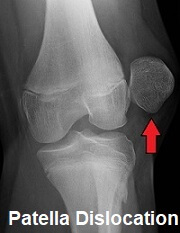

A dislocated patella is an extremely painful injury of the knee where the kneecap (patella) slips out of its normal position.

Kneecap dislocation causes immediate intense pain, disability and swelling as well as altering the shape of the knee. In most cases the kneecap dislocates laterally i.e. to the outer side of the knee due to the structure of the joint.

If a great enough force goes through the front of the knee, the kneecap shifts out the patella groove.

Patella Dislocation: where the kneecap is completely displaced

Most commonly, the kneecap shifts laterally due to the lateral ridge of the groove being lower than the medial ridge.

This should only be done by a qualified healthcare professional or there is a risk of further damage. An x-ray will be taken to ensure the bones are in the correct position and that there is no damage to other knee structures.